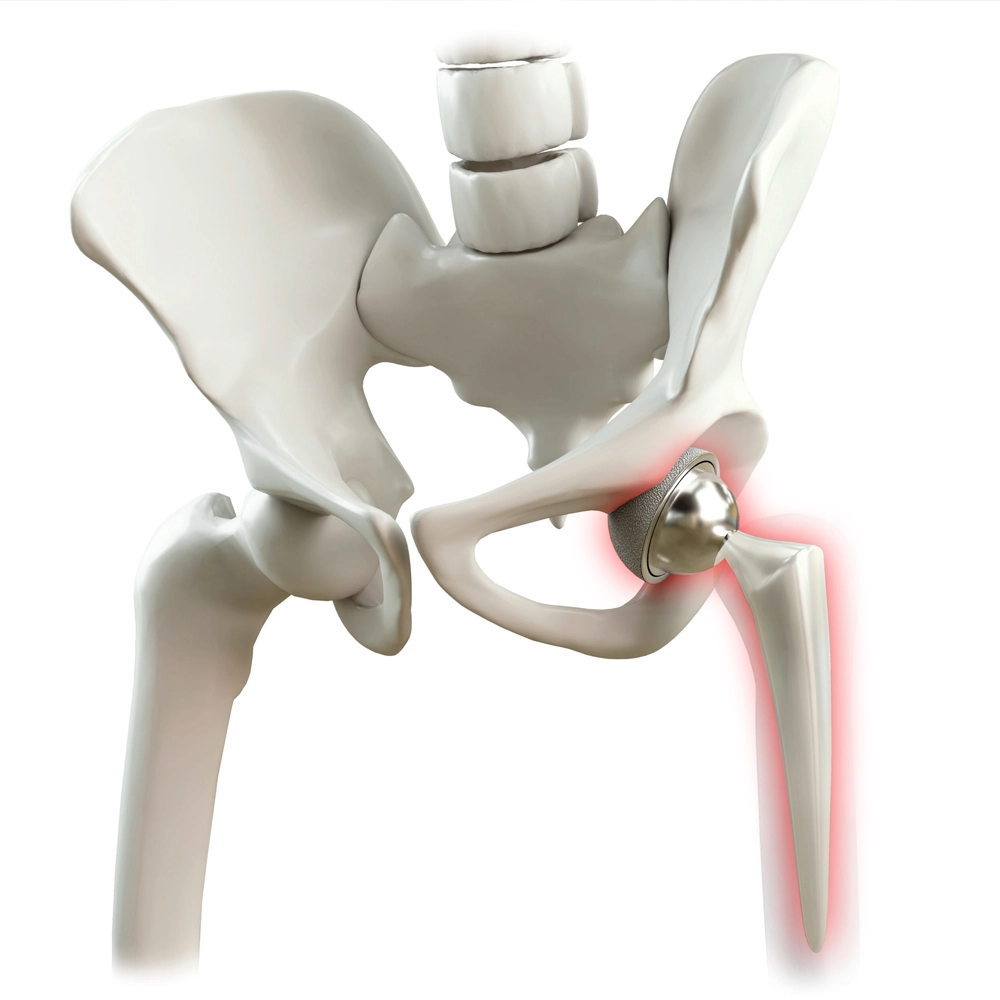

La chirurgie de remplacement de la hanche est une procédure orthopédique très efficace qui remplace une articulation de la hanche gravement endommagée par une articulation artificielle faite de matériaux durables comme le métal, la céramique ou le plastique. Cette chirurgie est une solution qui change la vie pour des conditions telles que l’arthrose avancée ou une fracture de la hanche, qui causent une douleur débilitante et une mobilité limitée. L’objectif principal de la chirurgie de remplacement de la hanche est d’éliminer la douleur, de restaurer la fonction articulaire et d’améliorer significativement la qualité de vie d’une personne.

Q : Quels sont les risques de la chirurgie de remplacement de la hanche ? R : Les risques comprennent l’infection, les saignements, les caillots sanguins, les lésions nerveuses et, dans certains cas, la luxation ou l’usure de la prothèse. Votre médecin expliquera ces risques en détail.

Q : Combien de temps dure un remplacement de la hanche ? R : Un remplacement de la hanche dure généralement de 15 à 20 ans. Cependant, sa durée de vie peut varier en fonction de votre niveau d’activité, de votre poids et de votre état de santé général.